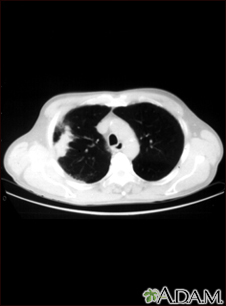

Lung with squamous cell cancer - CT scanBackLung with squamous cell cancer - CT scanThis CT scan shows a cross section of the lungs of a person with lung cancer. The two dark areas in the middle of the screen are the lungs. The light areas in the right lung (on the left of the screen) represent the cancer. E-mail FormEmail ResultsName:Email address:Recipients Name:Recipients address:Message: